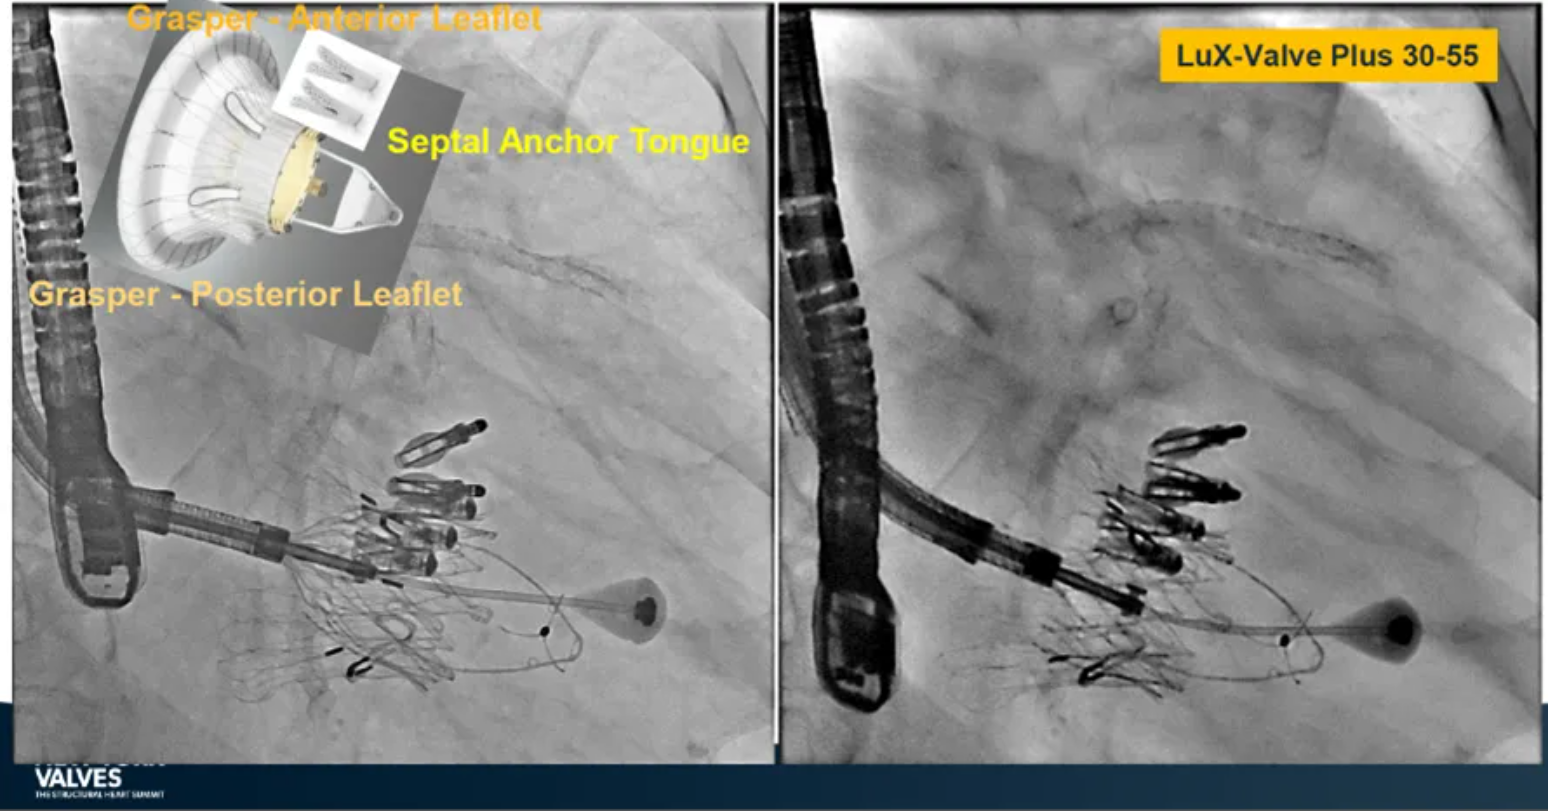

LuX-Valve Plus是健世科技(Jenscare,9877.HK)推出的全新一代經(jīng)頸靜脈三尖瓣置換系統(tǒng)(Transjugular Tricuspid Valve Replacement System),其創(chuàng)新性地采用頸靜脈作為手術(shù)入路,在不依賴徑向支撐力的情況下借助室間隔錨定、瓣葉夾持技術(shù)構(gòu)成其多重錨定結(jié)構(gòu),并通過自適應(yīng)編織環(huán)有效進(jìn)行心房側(cè)封堵,呈現(xiàn)更好的安全性和有效性。

來自中國香港瑪麗醫(yī)院(Queen Mary Hospital, Hong Kong, China)的Simon Lam教授在2024年紐約瓣膜會上分享了一例復(fù)雜案例,一名高齡男性患者在2年前行二尖瓣和三尖瓣TEER術(shù)式后繼發(fā)三尖瓣反流,遂再次行二尖瓣TEER術(shù)式和用LuX-Valve Plus行三尖瓣TTVR術(shù)式。

本次術(shù)式中,LuX-Valve Plus的植入緊隨二尖瓣修復(fù)術(shù)式之后,且并未取出前期植入的三尖瓣修復(fù)夾,這意味著LuX-Valve Plus在患者有過二尖瓣和三尖瓣修復(fù)夾植入情況下的兼容性,并且?guī)砹擞行У闹委熃Y(jié)果。此外,這不僅體現(xiàn)了LuX-Valve Plus可以與二尖瓣術(shù)式并行,更可以兼容三尖瓣原位的其他修復(fù)夾產(chǎn)品。